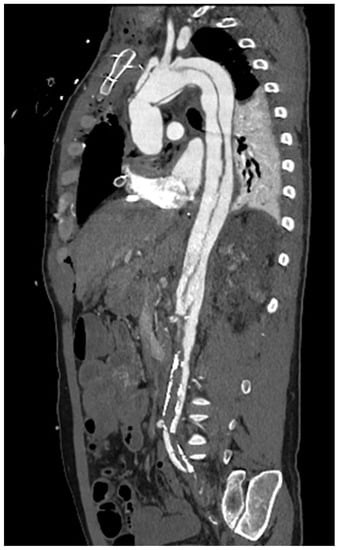

1.1. Computed Tomography

2. Vascular Imaging